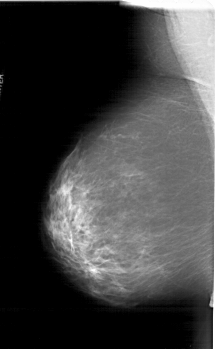

ics_version 1.0 filename A-1265-1 DATE_OF_STUDY 25 1 1995 PATIENT_AGE 48 FILM FILM_TYPE REGULAR DENSITY 3 DATE_DIGITIZED 23 7 1998 DIGITIZER HOWTEK 43.5 SEQUENCE LEFT_CC LINES 6556 PIXELS_PER_LINE 4111 BITS_PER_PIXEL 12 RESOLUTION 43.5 NON_OVERLAY LEFT_MLO LINES 6616 PIXELS_PER_LINE 4081 BITS_PER_PIXEL 12 RESOLUTION 43.5 NON_OVERLAY RIGHT_CC LINES 6646 PIXELS_PER_LINE 4066 BITS_PER_PIXEL 12 RESOLUTION 43.5 OVERLAY RIGHT_MLO LINES 6871 PIXELS_PER_LINE 3961 BITS_PER_PIXEL 12 RESOLUTION 43.5 OVERLAY |